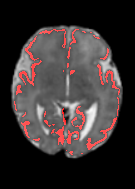

Fetal cortical plate segmentation is essential in quantitative analysis of fetal brain maturation and cortical folding. Manual segmentation of the cortical plate, or manual refinement of automatic segmentations is tedious and time-consuming. Automatic segmentation of the cortical plate, on the other hand, is challenged by the relatively low resolution of the reconstructed fetal brain MRI scans compared to the thin structure of the cortical plate, partial voluming, and the wide range of variations in the morphology of the cortical plate as the brain matures during gestation. To reduce the burden of manual refinement of segmentations, we have developed a new and powerful deep learning segmentation method. Our method exploits new deep attentive modules with mixed kernel convolutions within a fully convolutional neural network architecture that utilizes deep supervision and residual connections. We evaluated our method quantitatively based on several performance measures and expert evaluations. Results show that our method outperforms several state-of-the-art deep models for segmentation, as well as a state-of-the-art multi-atlas segmentation technique. We achieved average Dice similarity coefficient of 0.87, average Hausdorff distance of 0.96 mm, and average symmetric surface difference of 0.28 mm on reconstructed fetal brain MRI scans of fetuses scanned in the gestational age range of 16 to 39 weeks. With a computation time of less than 1 minute per fetal brain, our method can facilitate and accelerate large-scale studies on normal and altered fetal brain cortical maturation and folding.